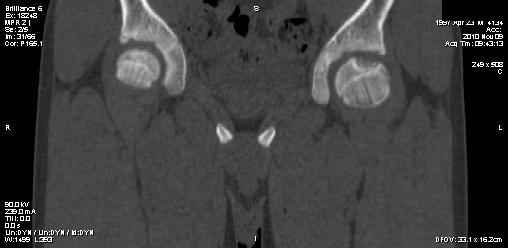

Мальчик 13 лет. В течение нескольких месяцев беспокоят боли в левом тазобедренном суставе.

При обследовании выявлена киста шейки левого бедра с сопутствующими изменениями в головке бедра, которые мы трактуем как дистрофические. Планируем вскрытие и санацию полости кисты передне-боковым доступом, костную пластику. Перед нами возникли следующие вопросы: для пластики использовать крыло подвздошной кости либо большеберцовую кость,либо их комбинацию, (полость большая,одним крылом можно не обойтись) или донорский аллотрансплантат с Коллапаном? Фиксировать ли? Если фиксировать, то чем? Доступны обычные угловые пластины либо АВФ.